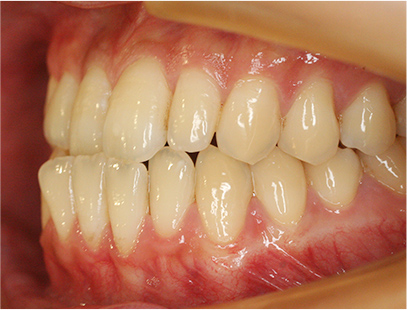

症例02|20代の男子

前歯部の反対咬合の症例

上下の前歯が反対咬合を主訴として来院されました。通常通り検査を行い「反対咬合」と診断されました。

治療計画

下の犬歯から後ろの歯をまずは後方に移動して、その後に上下の歯並びを綺麗に並べて前歯部の咬み合わせを改善することにしました。

矯正の種類

カリエールディスタライザー、上に裏側、下に表側のセラミック(白い矯正装置)

治療前の写真を治療後の写真を比べると、鼻の下がくぼんでいたのが改善されて口元が綺麗になった事が解ります。また歯並びは綺麗に並び上の歯が前に出て下の歯が後ろに移動して歯がしっかりと咬み合っています。

患者様に協力いただけたため、2年の治療期間で終了することができました。